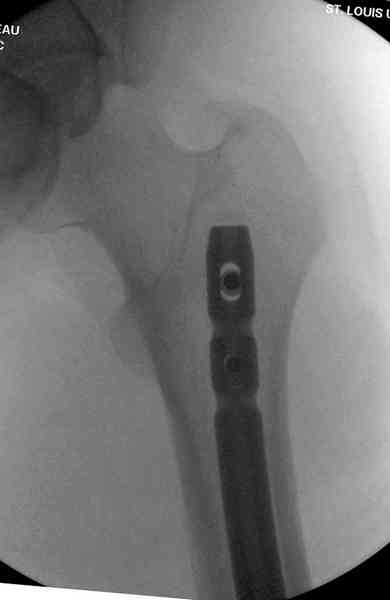

При высокоскоростных переломах редко можно встретить изолированную травму пилона, и в моей практике изолированные травмы большая редкость, поэтому, как дополнение к обсуждаемой теме, решил представить свежий, двухдневной давности случай.

Предыдущей сменой до 4:00 утра по поводу открытого перелома бедра, тибиал плато, пилон и надколенника сделана операция.

Пострадавшему 21 г., травма скоростная, после I&D с расширением раны, на бедре сделана операция ретроградным интрамедуллярным штифтом, остеосинтез с частичной резекцией надколенника и ушивание собственной связки.

На голень наружный фиксатор, рану на бедре ушили (рана была изнутри кнаружи всего 2 см). По протоколу травматических больных, до операции обследован ангиографически, (у больного дистально не смогли определить пульсацию) сосудистый хирург подтвердил проходимость на всем протяжении магистрального сосуда нижней конечности по снимкам ангиограмм.